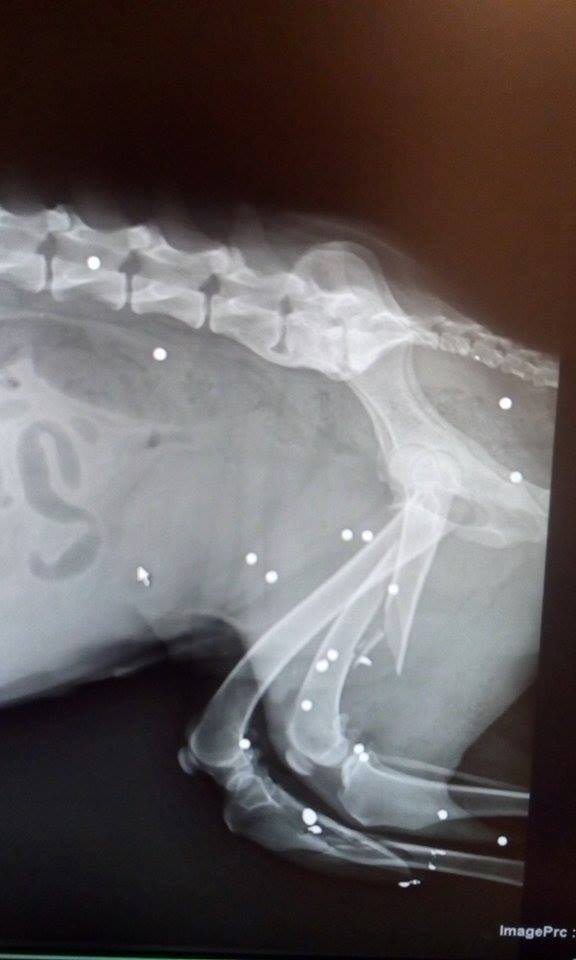

"She was found in a field, lying in her own blood, after being shot and left for dead in the middle of nowhere. Called Lucky by her rescuer, she was rushed to the clinic and benefited from the Homeless Animal Hospital program, which means she had top quality medical services for free. Both her hind legs were broken and dozens of bullet parts were found under the skin in different areas; she almost lost the fight after the first surgery that fixed her right back leg. A long recovery followed, but Lucky’s will to live touched everyone’s hearts. I was there for 4 days and got to witness her ordeal. I took her out in the yard a few times a day and fed her, such a dear sweetheart with such a will to survive. Although she had been through hell, she still found it in her heart to trust me. Lucky also had to have a blood transfusion, after which her health improved a lot.